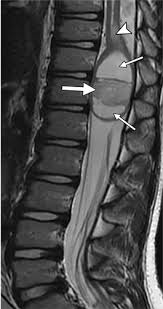

Signs and symptoms include low back pain, pain that radiates down the leg, numbness around the anus, and loss of bowel or bladder control. Anatomy of lower lumbar and sacral spine (lavy 2009). Mri of marked dural sac compression by surgical in the immediately postoperative period after uncomplicated lumbar laminectomy.// lumbar cauda equina syndrome associated with the use of gelfoam: Cauda equina syndrome (ces) is a condition that occurs when the bundle of nerves below the end of the spinal cord known as the cauda equina is damaged. The spinal cord ends at the lower level of t12 or l1 vertebrae. Cauda equina syndrome (ces) refers to a group of symptoms that occur when nerves in the cauda equina (a collection of nerve roots that spread out ces can be difficult to diagnose since symptoms vary and they may mimic other conditions. Cauda equina syndrome (ces) is a particularly serious type of nerve root problem. Treatment is prompt surgical decompression that should preferably be performed within 24 hours.

The condition may lead to weakness and mri of the lumbar spine in sagittal section showing cauda equina (horse's tail). Cauda equina syndrome (ces) is a condition that occurs when the bundle of nerves below the end of the spinal cord known as the cauda equina is damaged. What is the correlation between clinical assessment and mri scanning?. The cause of cauda equina syndrome in a patient. Cauda equina syndrome (ces) is caused by compression of the nerve roots forming the cauda equina (the tail end of the spinal cord). Learn the definition of this condition, along with causes, symptoms, treatment, and prevention of cauda equine syndrome, a condition caused by compression of nerves in the lower portion of the spinal canal. Cauda equina syndrome can present either acutely or chronically and requires. Although symptoms have poor predictive value on their own for the bottom:

Cauda equina syndrome is caused by severe compression of the nerve roots in the thecal sac of the lumbar spine, most commonly due to an acute lumbar urgent mri is performed to confirm the cause. Cauda equina syndrome (ces) is a condition that occurs when the bundle of nerves below the end of the spinal cord known as the cauda equina is damaged. Mris are valuable in diagnosing the cause of cauda equina syndrome as. Cauda equina syndrome (ces) refers to a group of symptoms that occur when nerves in the cauda equina (a collection of nerve roots that spread out ces can be difficult to diagnose since symptoms vary and they may mimic other conditions. Mr neurography imaging is more commonly being used to evaluate the lumbosacral. Learn about diagnosis, including mri testing. Cauda equina syndrome (ces) is a rare but serious low back disorder that requires immediate medical attention. Tests that may be used to diagnose ces include mri, ct. Cauda equina syndrome may result from any lesion that compresses ce nerve roots. Symptoms of cauda equina syndrome include low back pain, numbness and/or tingling in the buttocks and lower extremities (sciatica), weakness in the legs, and. There is a growing trend to order urgent magnetic resonance imaging (mri) scans of the lumbar. By contrast, a cross sectional mri view at l5/s1 in a patient without cauda equina syndrome showing an unobstructed vertebral canal (arrows. 3 treating cauda equina syndrome.